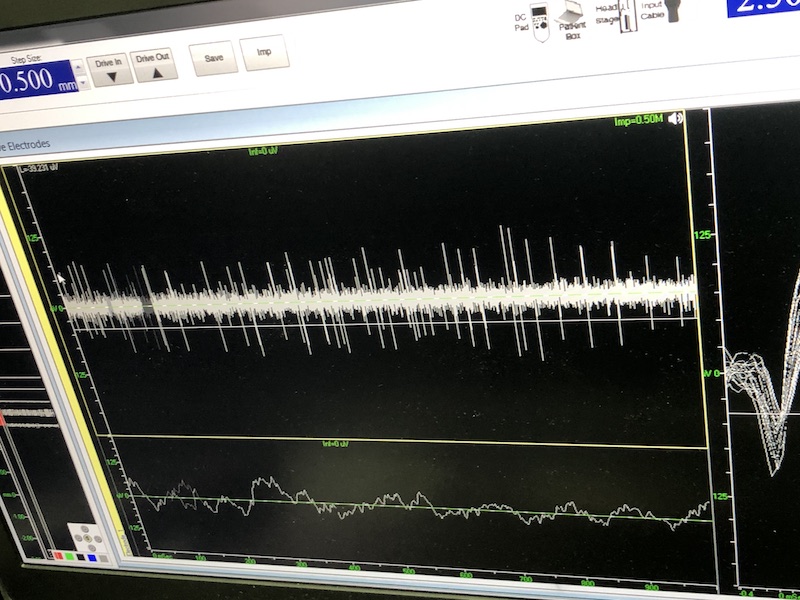

與此同時,檢測電極實時記錄電極末端每一點處的電信號,當(dāng)電極逐漸接近手術(shù)規(guī)劃靶點時,借助電信號的特征,醫(yī)生可以判斷電極是否已經(jīng)沿長軸植入患者顱內(nèi)的目標(biāo)核團(tuán),以及植入的準(zhǔn)確長度。下圖中,檢測信號屬于典型的核團(tuán)信號,證明電極已經(jīng)抵達(dá)相對理想的植入位置,記錄下此刻的位置后,即可在相應(yīng)位置植入刺激電極。

檢測核團(tuán)信號